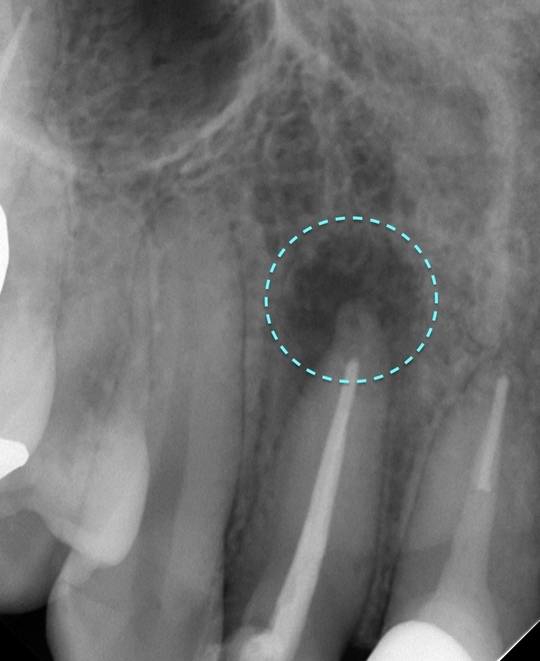

自費根管治療症例4 治療前(外科的歯内療法)

「前歯にニキビみたいなものができた」

離れていますが真ん中が原因歯です

治療はしてありますが、根の先が黒ずんで見えます

唇側の顎骨が溶けて穴が空いています